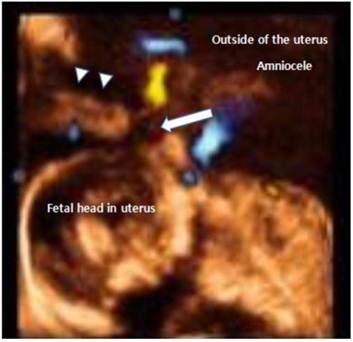

Fig 2

Transabdominal 3D US. Through the focal defect in the uterus, the umbilical arteries and veins were colorized by 3D doppler sonography. The umbilical cord appears as a long, extended, tubular structure. The anterior aspect of the fetal head was abutting the umbilical cord and the rupture site and umbilical cord closely. arrow: ruptured site of the uterus; arrow head: intact uterus wall.

A 30-year-old patient, with a history of 2 vaginal deliveries and amniocentesis 1 week prior to admission, was referred at 23 weeks gestation for evaluation of a large abdominal cyst and abdominal discomfort. Abdominal discomfort occurred 2 days before visit, and was aggravated on the day of visit. The patient was a non-smoker and had no underlying diseases. She had not consumed alcohol during her pregnancy. On examination, the abdomen was tender; the abdomen protruded more than the right side than on the left side. Her blood pressure was 120/70 mmHg; heart rate 100 beats/min and body temperature, 36.8℃. We performed transabdominal and transvaginal 2D ultrasound; a large cystic mass was noted on her left adnexa area and oligohydramnios with intrauterine fetus was noted. The cervix was closed and measured 4 cm in length. Three-dimensional (3D) ultrasound (ACCUVIX, Medison, Seoul) was performed and we noted that the umbilical cord had herniated through uterus wall and about 15 X 15 cm sized large amniotic sac had herniated through the uterine wall, 3D image suspected uterine ruptured part (2 cm) of the uterus on the left fundal uterine wall (Fig. 1 and Fig. 2). Laboratory analysis showed a hemoglobin level of 11.3g/dL, a white blood cell count of 15350 cells/mm3 and a C-reactive protein of 1.34 mg/dL. During the hospital observation period (5 hours), the patient complained of vaginal bleeding and progressive lower abdominal pain. Five hours later, the patient's abdominal pain and vaginal bleeding worsened; the blood pressure dropped to 100/80 mmHg and the pulse was 120 beats/min. The treatment team decided to proceed with exploratory laparotomy under general anesthesia. During the procedure and upon entering the abdominal cavity, the entire amniotic sac containing the fetus protruded through a 4 cm ruptured left fundal uterine wall and about 1000 mL hemoperitoneum was detected (Fig. 3). The fetus was delivery by Cesarean section using a classic uterine incision. The fetus expired (male, 700 g) immediately after delivery. Amniotic fluid was clear and not odorful. After removal of the placenta, a double layer of 2-0 chromic was used to close the uterine defect. The patient was discharged 5 days later.

There is little doubt that prompt recognition of uterine rupture and expeditious recourse to laparotomy remain the critical factors influencing morbidity and mortality of the mother and of the fetus. An amniocele is a herniation of the amniotic sac through a uterine defect [7]. Our case was initially diagnosed as a large abdominal cystic mass, but after 3D-ultrasound assisted identification of the uterine rupture, and by finding amniocele connected to the defect, we ensured an accurate diagnosis. The diagnosis could have been possible using 2D ultrasound by close observation, but with 3D ultrasound, 3-dimensional observation on the uterine defect was more helpful towards making a definite diagnosis. In addition, when the defect was located at the posterior of uterus where it was difficult to make an observation with 2D ultrasound, 3D ultrasound had superior values to 2D ultrasound. Since antepartum uterine rupture is a life threatening event to the mother and fetus, a rapid and accurate diagnosis is very important to improve prognosis.